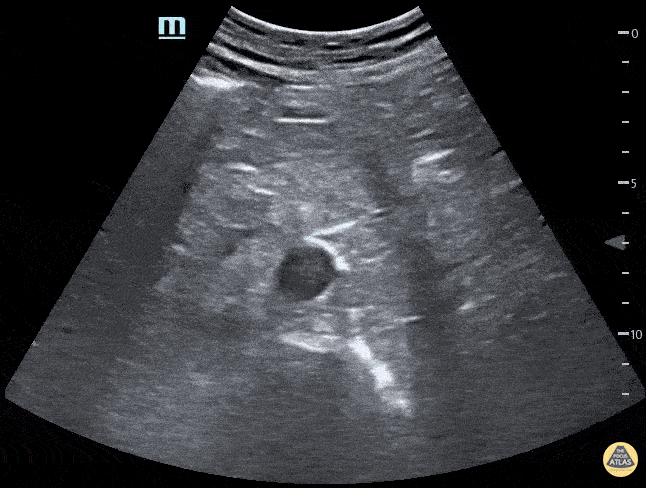

Renal/GU - Horseshoe Kidney Transverse

Horseshoe kidney. No kidney was identified in either flank area, this anterior abdominal view shows one large kidney that is anterior to the Aorta. Contributed by: Marion Memmott, DO; Michael Bernard, DO; Central Michigan University Emergency Medicine Residency